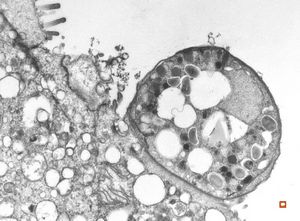

M,54y. | Whipple disease

Whipple disease